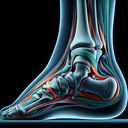

МРТ гомілково-ступневогу суглобу

Магнітно-резонансна томографія (МРТ) гомілково-ступневого суглобу є безпечним і неінвазивним методом діагностики, що дозволяє отримати детальні зображення структур м’яких тканин, кісток, сухожиль і зв'язок. МРТ надає можливість: 1. **Оцінити стан зв’язок і сухожиль** – виявлення розривів чи запалень...